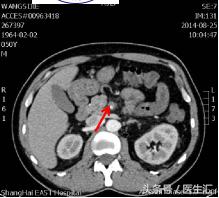

第7天清晨2:00夜班医生查体全腹部平软,但是上腹部有一点点轻压痛,无反跳痛,麦氏点无压痛,夜班医师给与654-2解痉处理,但是效果还是不满意。所以做了一个中上腹CT平扫示:肠系膜上动、静脉周围渗出性改变,建议增强扫描。第7天早上10:00做中上腹增强CT示:肠系膜上动脉内低密度影,考虑附壁血栓形成,局部管腔重度狭窄。这个时候这个患者的诊断应该来说已经很明确了。于是请了相关科室的医生进行会诊,决定进行经皮选择性肠系膜动脉造影+肠系膜动脉溶栓术。患者溶栓导管行脉冲式注射尿激酶溶栓,患者术后24h出现便血4次,200ml/次。